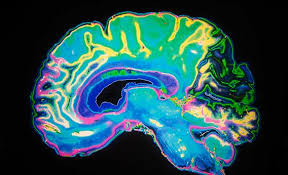

تاکنون بیش از 20 تحقیق در رابطه با تأثیر پورنوگرافی بر مغز انجام شده است. همگی این تحقیقات ثابت کرده تماشای فیلمهای پورنو آسیبی معادل مصرف مواد مخدر یا الکل بر مغز دارند. نتایج تحقیق جدیدی که محققان دانشگاه کمبریج انجام دادند، نشان میدهد مغز افرادی که گرایش مکرر به تماشای فیلمهای پورنو دارند، همانند مغز افراد الکلیک است. در این تحقیق، به کمک تکنیک تصویربرداری MRI مشخص شد تماشای پورنو، بخشی از مغز را که مسئول خلاقیت و احساس خوشبختی است، هدف میگیرد.

ترشح دوپامین به میزان بالا در هنگام تماشای فیلم پورنو، باعث خستگی مناطق جلویی مغز میشود که در تصمیمگیری و کنترل رفتار دخالت دارد. دوپامین برای حس خوشبختی حیاتی است، اما وقتی فردی به تماشای این نوع فیلمها وابسته میشود، ترشح دوپامین افزایش مییابد و این موضوع سلولهای تولیدکنندهی آن را خسته میکند. در نتیجه ترشح به مرور کم میشود و رسیدن به حس خوشبختی در فرد به تدریج کمرنگ خواهدشد و فرد به ناچار برای رسیدن به آن راههای دیگری از جمله اعتیاد یا مصرف الکل را انتخاب میکند، که این موضوع نیز مجدداً به مغز آسیب میرساند.

محققان در بررسیهای خود روی موشها، منطقهی مربوط به حس خوشبختی را تحریک کردند که ترشح زیاد ترکیبات شیمیایی در مغز در نهایت به مرگ موشها انجامید. در انسان ترشح زیاد این ترکیبات باعث خستگی شدید مغز میشود و این مسئله، حافظه، تمرکز، توجه و قدرت تصمیمگیری را تحت تأثیر قرار میدهد. مغز افرادی که به تماشای فیلمهای پورنو اعتیاد دارند، صرفاً تحریک میشود و این موضوع روی کارکرد مغزی و وضعیت روانی این افراد اثر منفی میگذارد.

در سال 2002 تحقیقی روی افراد معتاد به کوکایین انجام و مشخص شد که مناطقی از لوب پیشانی در این افراد آسیب دیده است. در سال 2004 تحقیق دیگری به اثبات رساند اعتیاد باعث افزایش وزن بخشی از مغز میشود. تماشای پورنوگرافی نیز آثار مشابهی بر مغز دارد. بررسیهای جدیدتر نشان داده، وابستگی به تماشای تصاویر جنسی و فیلمهای پورنو باعث تغییر خود به خود و شدید ساختار مغز میشود.